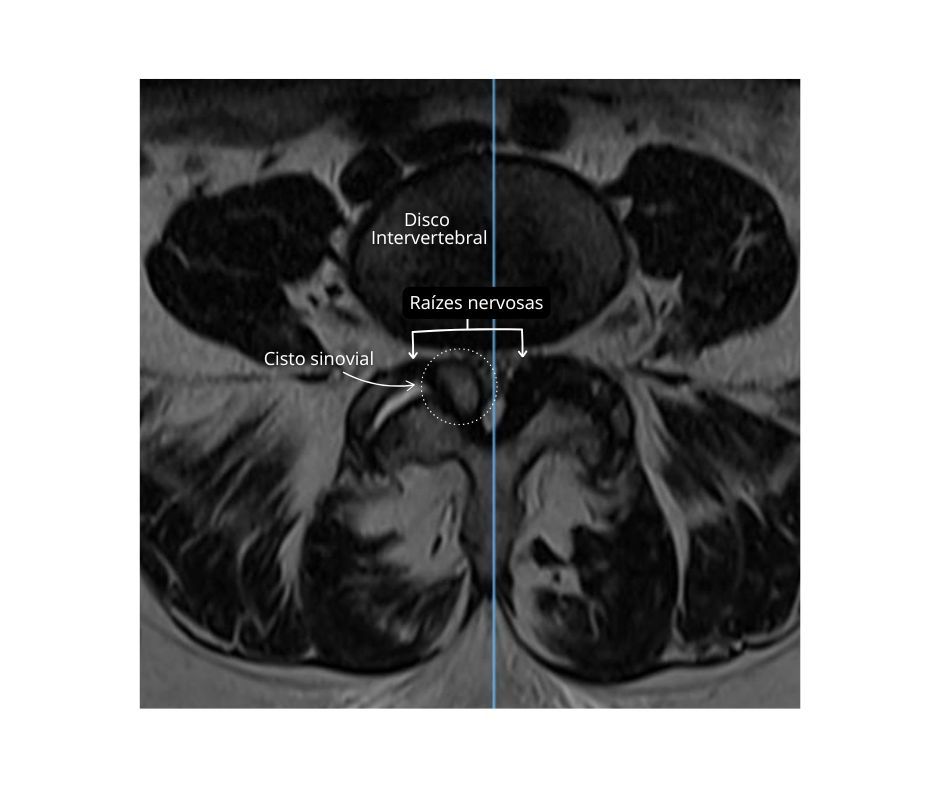

• Cisto facetário: é uma pequena bolsa de líquido que se forma nas articulações posteriores da coluna (facetas), geralmente como consequência de artrose. Apesar de pequeno, pode comprimir raízes nervosas e causar dor lombar intensa, irradiada, além de formigamento ou dormência. Muitas vezes é confundido com hérnia de disco, mas exige avaliação específica para diagnóstico preciso.

O cisto facetário pode ser o responsável pela dor lombar e sintomas irradiados, como dormência e perda de força nos membros.